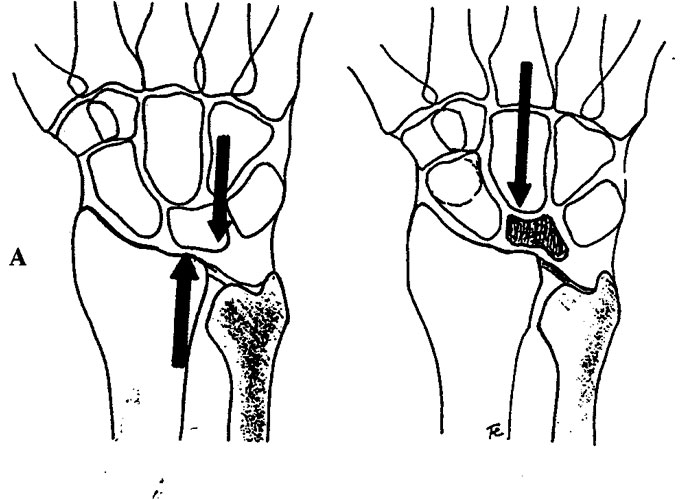

Factores mecánicos y anatómicos

Algunas variantes anatómicas pueden influir en la distribución de las cargas sobre el semilunar. Entre ellas, se ha descrito con frecuencia la asociación con el cúbito minus o cúbito corto, así como con determinadas formas anatómicas del semilunar.

Radiografía simple.

La radiografía puede mostrar cambios en la densidad del semilunar, esclerosis, pérdida de altura, colapso o signos degenerativos en fases más avanzadas. También puede ayudar a identificar variantes anatómicas asociadas, como el cúbito corto.

Técnicas de descompresión

Las técnicas de descompresión buscan disminuir la sobrecarga que soporta el semilunar. En pacientes seleccionados pueden plantearse osteotomías del radio o de otros huesos del carpo para redistribuir las cargas.